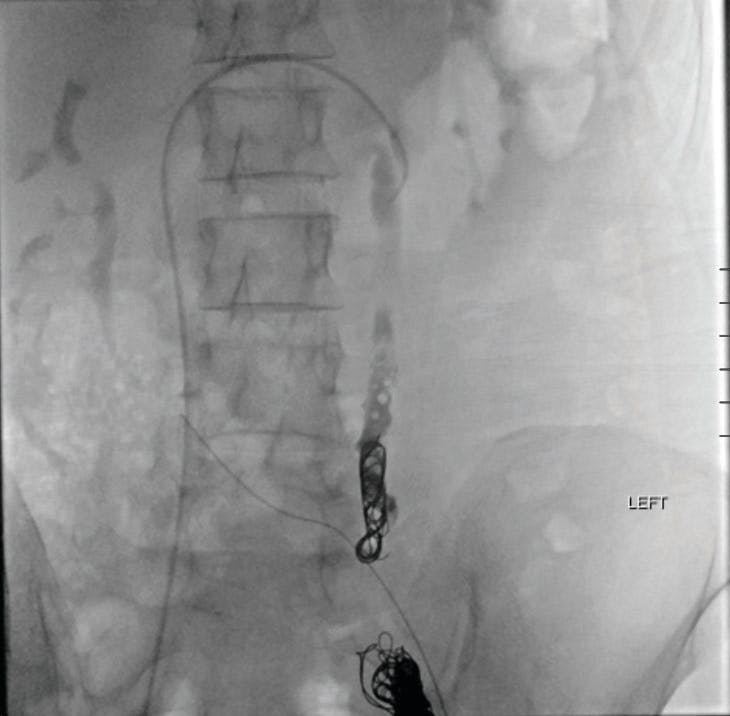

For this second procedure, Ruby XL Coils were selected. Although a similar packed volume was required, only three coils were needed compared with 10 coils on the left. This reduced both procedure time and cost without compromising effectiveness.

At follow-up, the patient reported complete resolution of all pelvic symptoms and expressed high satisfaction with her outcome (Figure 3).

Figure 3. Postembolization venogram showing bilateral ovarian vein coil embolization with no distal reflux into the pelvic varicosities.